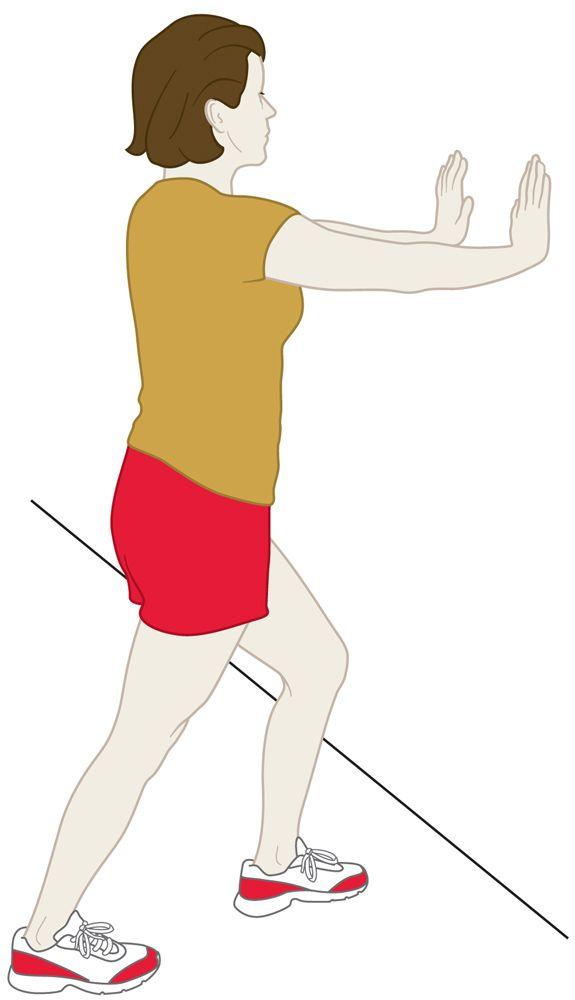

The following exercises and stretches can help to strengthen the calf muscles and reduce stress on the Achilles tendon.

Calf stretch. Lean forward against a wall with one knee straight and your heel on the ground. Place the other leg in front, with the knee bent. To stretch the calf muscles and the heel cord, push your hips toward the wall in a controlled fashion. Hold the position for 10 seconds and relax. Repeat this exercise 20 times for each foot. You should feel a strong pull in the calf during the stretch.